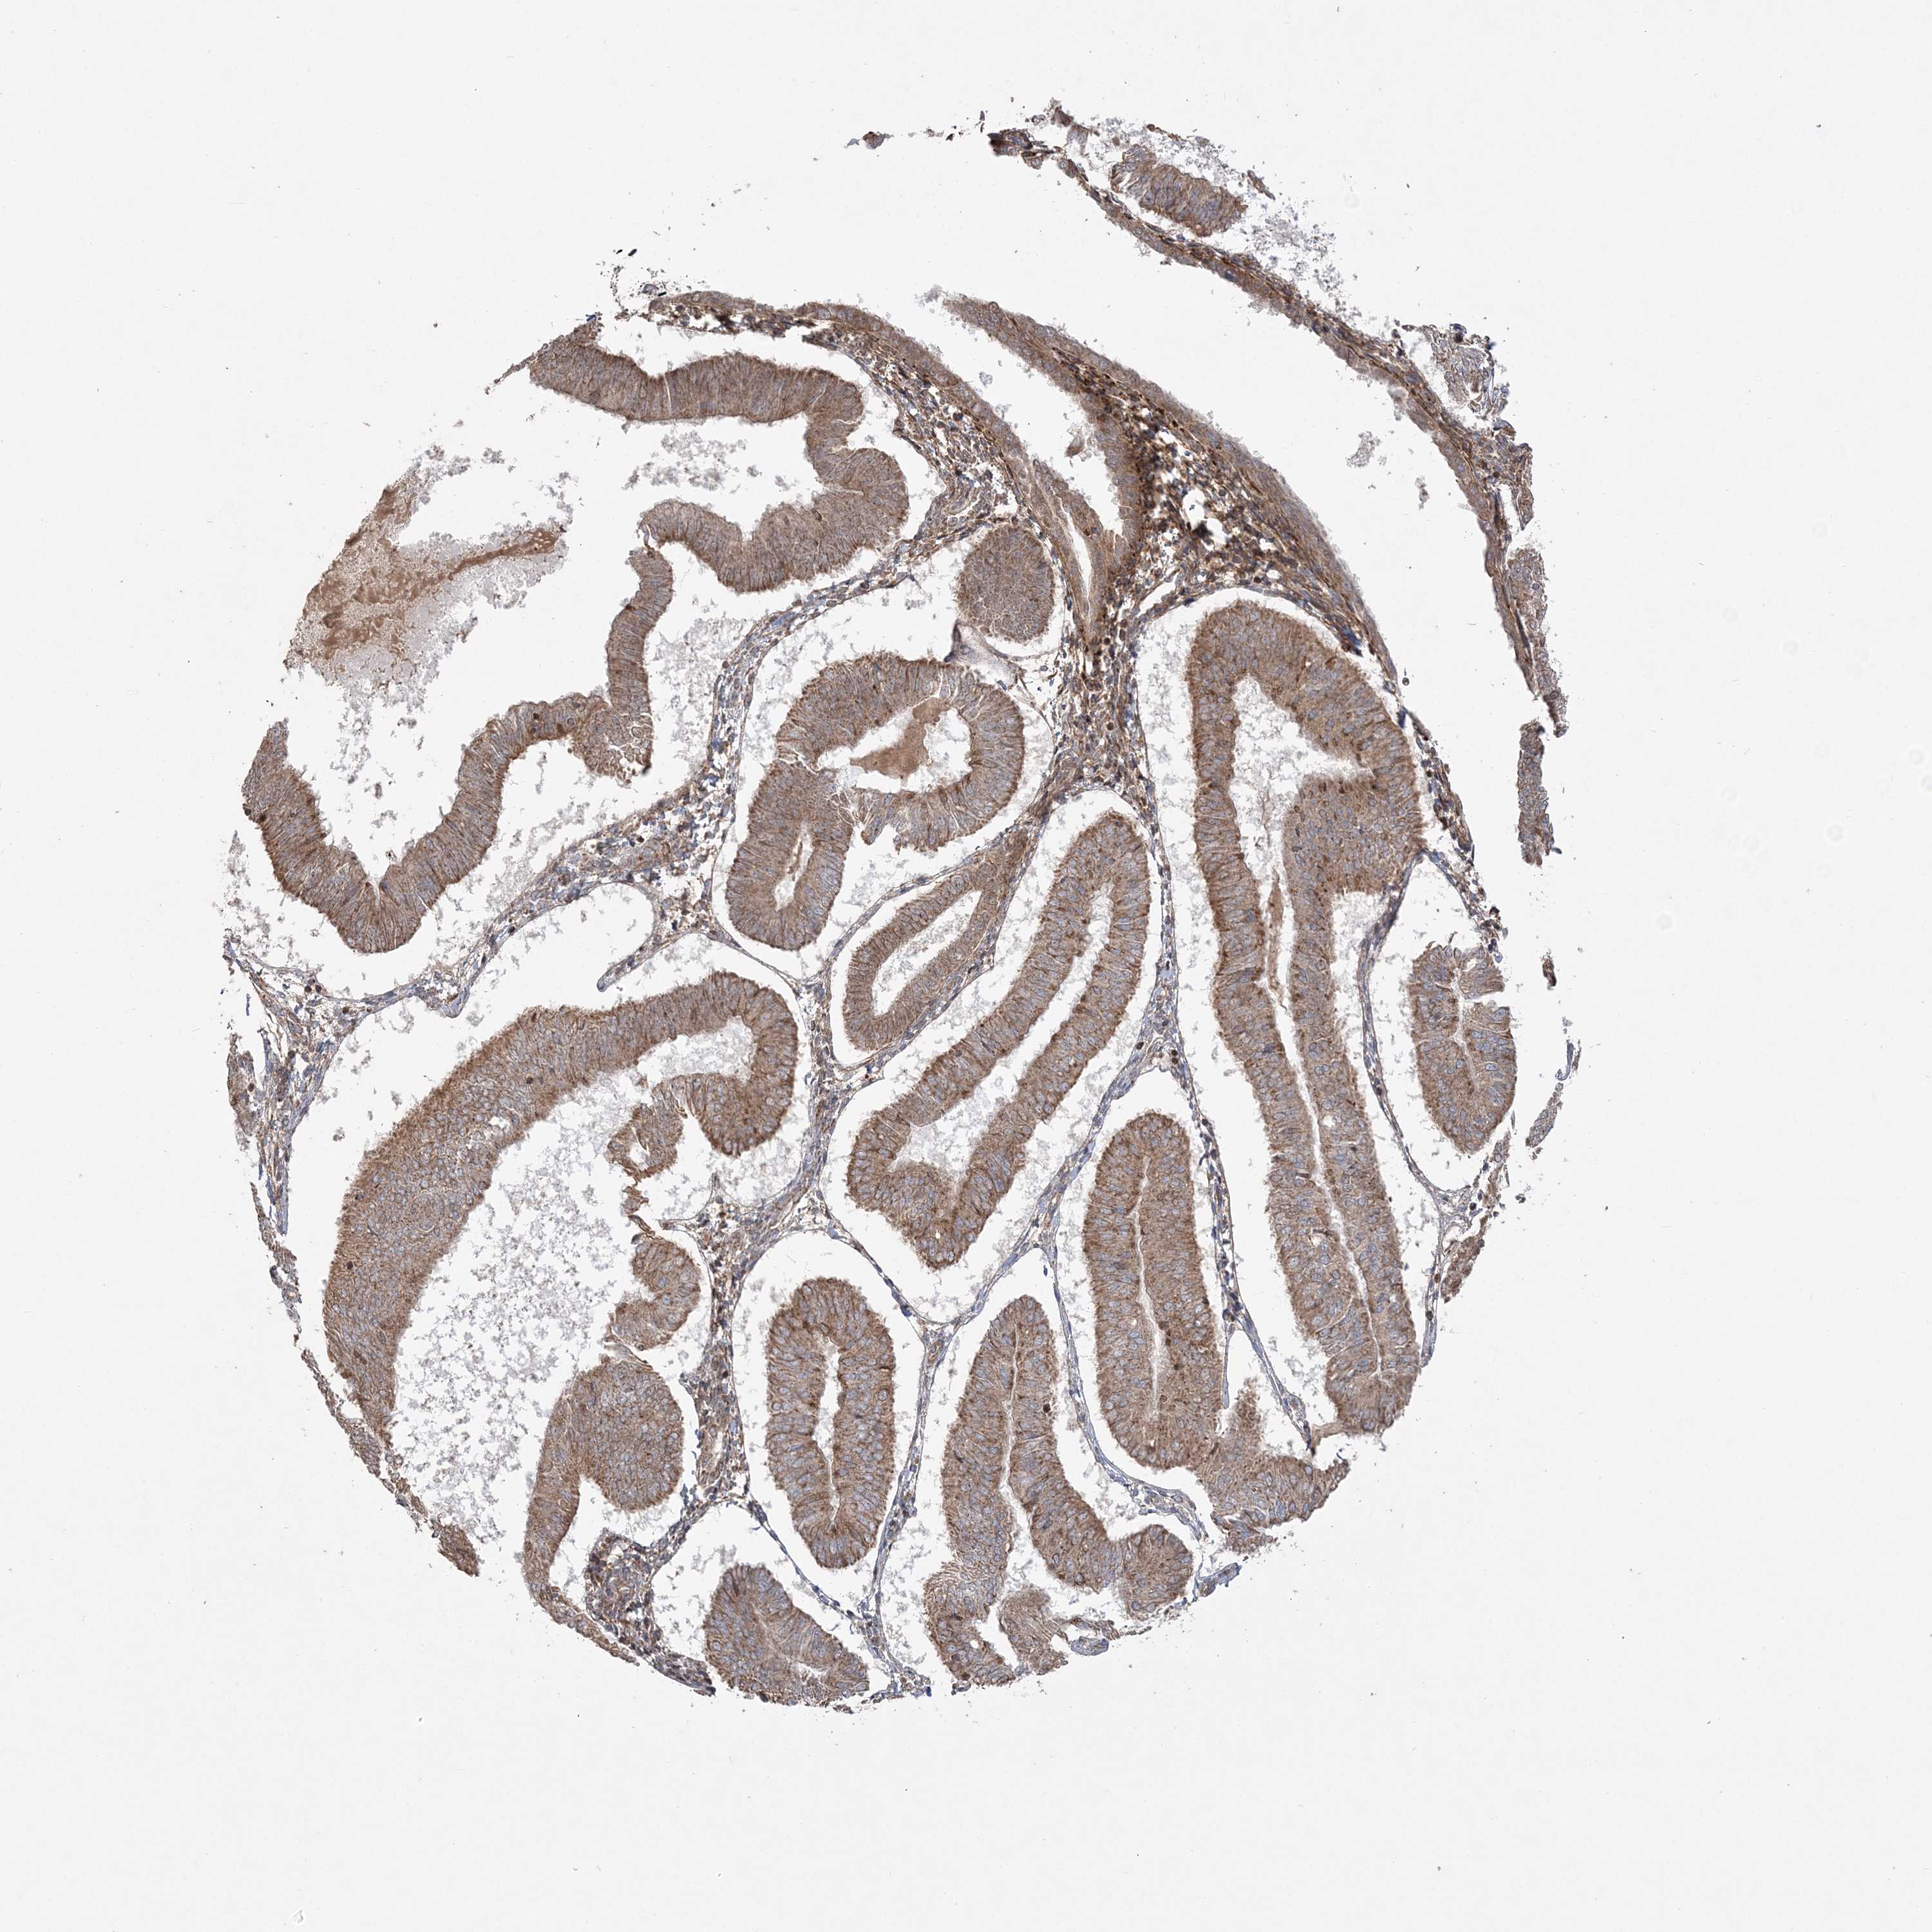

ENDOMETRIAL CANCER - Protein expressioni

A mouse-over function shows sample information and annotation data. Click on an image to view it in a full screen mode. Samples can be filtered based on level of antibody staining by selecting one or several of the following categories: high, medium, low and not detected. The assay and annotation is described here.

Note that samples used for immunohistochemistry by the Human Protein Atlas do not correspond to samples in the TCGA dataset.

Antibody stainingi

Antibody staining in the annotated cell types in the current human tissue is reported as not detected, low, medium, or high, based on conventional immunohistochemistry profiling in selected tissues. This score is based on the combination of the staining intensity and fraction of stained cells.

Each image is clickable and will lead to virtual microscopy that enables deeper exploration of all samples and also displays staining intensity scores, fraction scores and subcellular localization as well as patient and tissue information for each sample.

Antibody HPA036560

Antibody HPA036561

Staining

High

Medium

Low

Not detected

Intensity

Strong

Moderate

Weak

Negative

Quantity

>75%

75%-25%

<25%

None

Location

Nuclear

Cytoplasmic/membranous

Cytoplasmic/membranous,nuclear

Adenocarcinoma, NOS